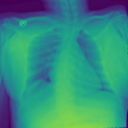

4.1.2 Lung Segmentation

Additionally, we evaluate the performance of DiffeoNN on real-world data, using a dataset with chest X-ray images and their ground-truth lung segmentation from (RSUA, 2023). The original dataset contains images and corresponding ground-truth segmentations into three different classes (“Non-Covid”, “Covid”, and “Non-Covid-Pneumonia”). We combine the images and corresponding ground-truth segmentations of the initial three classes into one dataset, which is then split into a training dataset of image-segmentation pairs, a validation dataset of pairs, and a test dataset of pairs. We then proceed as in Section 4.1.1 to create a dataset of diffeomorphically transformed images.

Benchmarking Results

We apply DiffeoNN, the inner U-Net (naïve approach) and an augmented U-Net, which is trained on the original and the diffeomorphically transformed training dataset, to the diffeomorphically transformed images from the test dataset. Visual results are presented in Figure 4 and further details on the experimental setup, training, and additional examples in Appendix B. The results closely mirror those obtained on the synthetic dataset, see Table 1(b). On average, DiffeoNN outperforms the naïve approach, validating the effectiveness of our approach. The canonicalisation step pushes the input image towards the training dataset by moving the thorax to a more central position and aligning the shoulders, which makes it easier for the inner U-Net to predict an accurate lung segmentation. While our method performs slightly below the augmented gold-standard baseline, it offers more flexibility by not relying on data augmentation or retraining, making it a practical and robust solution in real-world applications.